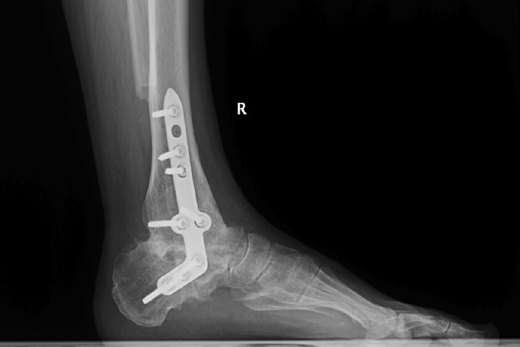

Figura 15. Control posquirúrgico tras la corrección de la pseudoartrosis en varo.

- Control posquirúrgico tras la corrección de la pseudoartrosis en varo (Figura 15).